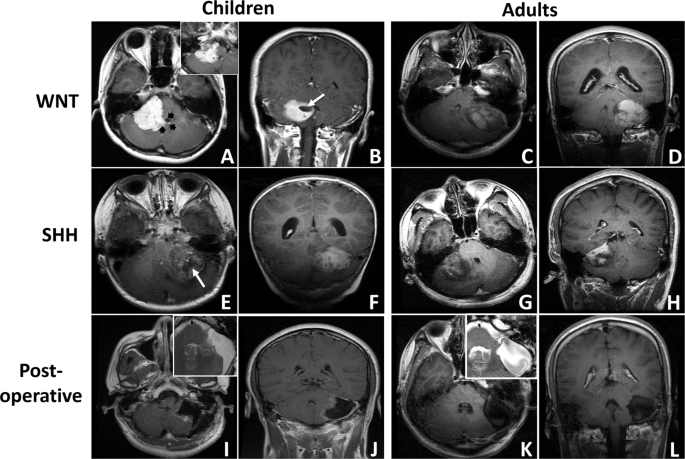

The MRI study showed that 9 tumors (60.0%) were located on the left, and 6 tumors (40.0%) were located on the right (Fig. 1A–H). The mean tumor diameter was 4.4 ± 0.87 cm (range 3.5–5.7 cm). A well-defined margin was observed in 8 cases (53.3%), and peritumoral edema was seen in 7 cases (46.7%). None or small focal cysts (<1 cm) were present in 6 cases (40.0%), whereas cysts larger than 1 cm were present in 9 cases (60.0%; Fig. 1B,E, white arrow). After contrast administration, solid enhancement was seen in 8 cases (53.3%; Fig. 1A–D), while heterogeneous or minimal enhancement was seen in 7 cases (46.7%; Fig. 1E–H). The floor of the 4th ventricle was involved in 3 cases (20.0%), while the prepontine cistern was involved in 1 case (6.7%; Fig. 1A, black arrow). Spinal metastasis was found in 1 case (6.7%). CT scans showed that lesions with high or heterogeneous density located in the CPA, coming into contact with the posterior edge of the petrous bone (Fig. 2). Hemorrhage or mineralization was identified in 5 cases (33.3%; Fig. 2C,D, white arrow). The IAC was not dilated in all cases. No substantial difference in radiological features was observed between adult and childhood patients (Supplementary Table 1).

Exemplary magnetic resonance imaging (MRI) of cerebellopontine angle medulloblastoma (MB) (T1-weighted post-contrast axial and coronal MRIs). (A,B) A pediatric CPA WNT-MB with solid enhancement is shown (black arrow: the invasion of the 4th ventricle is shown; white arrow: the focal cyst is shown; inset: prepontine cistern involvement). (C,D) An adult CPA WNT-MB with solid enhancement is shown (white arrow: the focal cyst is shown). (E,F) A pediatric CPA SHH-MB with heterogeneous enhancement is shown. (G,H) An adult CPA SHH-MB with heterogeneous enhancement is shown. (I,J) Postoperative images of a pediatric CPA SHH-MB are shown (inset: T2-weighted MRI; preoperative images: E,F). Damage to the left cerebellar hemisphere is shown. (K,L) Postoperative images of an adult CPA WNT-MB are shown (inset: T2-weighted MRI; preoperative images: C,D). Compression of the left cerebellar hemisphere without erosion is shown.

Histopathology revealed classic features of MB (CMB) in 12 cases (80.0%), while 3 cases had a diagnosis of DNMB (20.0%; Table 1). Molecular classification analysis showed that 15 CPA MBs consisted of 5 WNT tumors (33.3%) and 10 SHH tumors (66.7%). No significant difference in histopathological subtype or molecular subgroup was observed between adult and childhood patients (Supplementary Table 1). A striking association between biologic subgroups and radiological features was observed. Based on the pre- and postoperative MRI results and intraoperative reports, we found that all WNT-MBs were derived from the brainstem (P = 0.004) and grew exclusively outside the cerebellum, whereas SHH-MBs resided in the cerebellar hemispheres (P = 0.002; Fig. 1; Table 2). Moreover, solid enhancement was observed in all WNT-MBs (6/6; 100.0%) and in 30% of SHH-MBs (3/10; P = 0.044; Fig. 1). No significant difference was observed between two molecular subgroups according to the other clinical and radiological features (Table 2).